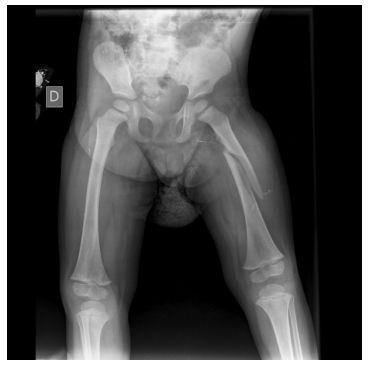

49. 2 歲大小孩從床鋪上跌落地,左大腿腫痛,X 光如下圖。下列何者是最適當的處置? (A)垂直懸吊皮膚牽引 (B)骨骼牽引 (C)用折頂迴旋法復位後,再以夾板固定 (D)水平位持續牽引